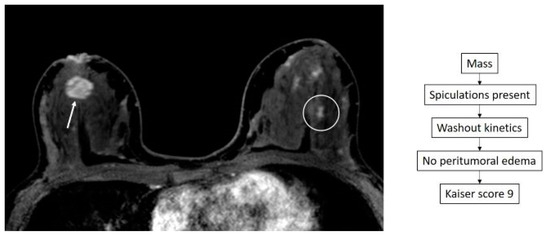

- Dietzel, M.; Baltzer, P.A.T. How to Use the Kaiser Score as a Clinical Decision Rule for Diagnosis in Multiparametric Breast MRI: A Pictorial Essay. Insights Imaging 2018, 9, 325–335. [Google Scholar] [CrossRef] [PubMed]